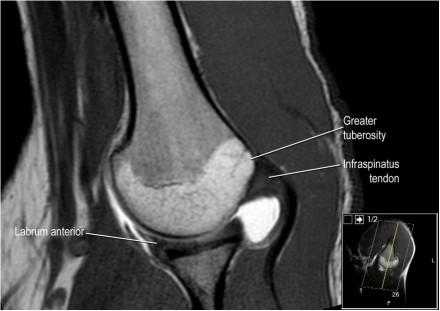

Изображение задних отделов плечевого сустава.

Отображены надостная, подостная и малая круглая мышцы и их сухожилия. Все они прикрепляются к большому бугорку плечевой кости. Сухожилия и мышцы манжеты вращателей участвуют в стабилизации плечевого сустава во время движения. Без манжеты вращателей головка плечевой кости частично сместилась бы из суставной впадины, уменьшив силу отведения дельтовидной мышцы (мышцы вращательной манжеты координирует усилия дельтовидной мышцы). Повреждение манжеты вращателей может привести к смещению головки плечевой кости кверху, в результате вызвая высокое стояние головки плечевой кости.